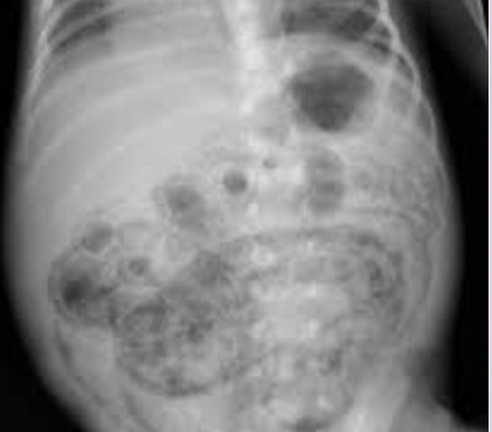

18 mon old with off/on abdominal pain X 12 hours and 1X vomit. This image is obtained. The exam may show this on abdominal exam and this on diaper exam

What is sausage mass and currant jelly stools

What is intussusception and HSP